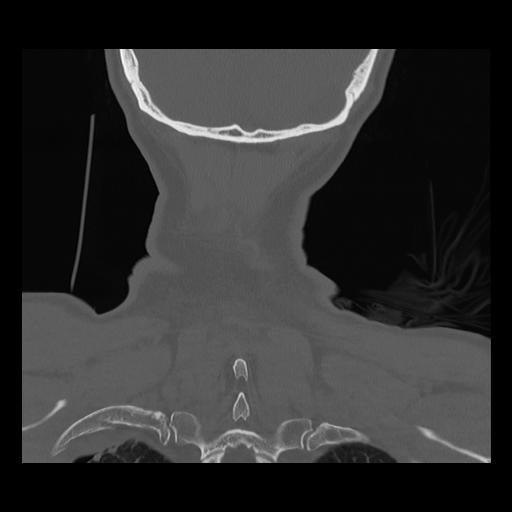

16 HUESO,,Coronal,2.000,HUESO,Coronal,